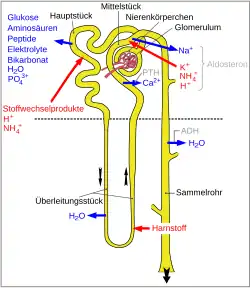

Physiological basics

The kidney is a vital organ with a variety of tasks. It plays an important role in maintaining the water, electrolyte and acid-base balance, in the excretion of toxic metabolic degradation products such as urea and in the recovery of valuable substances such as glucose, amino acids, peptides and minerals initially filtered out of the blood during ultrafiltration in the renal corpuscles. In addition, endogenous and exogenous substances are metabolized and broken down in the kidneys—the kidney is therefore a central metabolic organ alongside the liver. Finally, some hormone-active substances such as renin, erythropoietin and calcitriol (active form of vitamin D3). As a result, the organ plays an important role in the regulation of blood pressure, new blood formation and the calcium and phosphorus balance and thus the bonemetabolism. As carnivores, cats are particularly dependent on the intake of animal proteins because glucose formation from amino acids is their most important energy source. The enzymes of amino acid degradation are adapted to the high protein intake and their activity is largely independent of the protein supply in the diet, so that cats break down endogenous proteins (especially from the muscles) when there is a lack of protein intake (catabolic metabolic state).[1][2] Fleisch und Innereien enthalten darüber hinaus für die Katze lebensnotwendige Nährstoffe wie beispielsweise Vitamin A, Taurin or arachidonic acid.[2] Compared to a normal human diet, cats consume around six times as much phosphate in their diet with standard cat food. This makes it difficult to achieve a similar phosphorus reduction in cat food as is aimed at in human medicine for human kidney diets.[3]

Symptoms of the disease only appear at an advanced stage, when more than two-thirds of the original kidney function has already been lost. This is due to the body's own compensatory mechanisms and the kidney's reserve capacity, which can compensate for the reduced kidney function for a long time and maintain the excretion of urine-requiring substances.[3][4] With the loss of functioning nephrons—the functional structural unit of the kidney—the filtering capacity of the renal corpuscles (glomerular filtration rate) decreases and with it the excretory capacity for urinary substances. Acute damage to the tubules can regenerate again if the basement membrane is preserved. However, if a section of the nephron is irreversibly damaged, the entire nephron dies.[5]

As a result of the accumulation of phosphate in the blood (hyperphosphatemia) and the reduced formation of calcitriol in the remaining main parts, there is a drop in the calcium blood level (hypocalcemia) and increased parathyroid hormone is released from the parathyroid gland. Chronic kidney disease leads to hyperparathyroidism in 84% of cases (secondary renal hyperparathyroidism).[8] Among other things, the parathyroid hormone causes calcium and phosphate to be released from the bones, which ultimately leads to renal bone disorders and calcification of the kidneys, skin, heart and blood vessels. In the kidneys, this calcification contributes to further destruction of the kidney tissue. The reduced responsiveness of the parathyroid cells to calcium disrupts the negative feedback of parathyroid hormone secretion, so that parathyroid hormone continues to be secreted despite the increase in calcium levels. As less phosphate reaches the renal tubules due to the reduced filtration rate, the inhibitory effect of parathyroid hormone on reabsorption in the main body has only a minor effect on the blood phosphate level.[8][9]

The loss of nephrons and the associated decrease in the number of sodium ion channels leads to a decrease in the concentration gradient in the kidney. However, this is the driving force for water reabsorption in the mid-piece and—in the presence of ADH—also in the collecting ducts. The result is a loss of water via the urine and thus drying out of the body, which is exacerbated by the loss of fluid during vomiting.[7]

One consequence of the kidneys' reduced ability to excrete hydrogen ions, phosphate and sulphate and the excessive loss of bicarbonate is the metabolic acidification of the blood (metabolic acidosis).[10] Metabolic acidosis occurs in 80% of cats with chronic kidney disease.[11]

With increasing kidney damage, the autoregulation of renal blood flow, which normally ensures that the blood flow and thus the filtering capacity up to a threshold of 60 mm Hg are independent of the general blood pressure, is also impaired. As a result, kidney performance is reduced at low blood pressure and, in the case of high blood pressure often associated with chronic kidney disease, further damage occurs due to pressure overload of the renal corpuscles.[12] The increase in blood pressure is due to hardening of the blood vessels in the area of the renal corpuscles, the reduced formation of vasodilating prostaglandins and activation of the renin-angiotensin-aldosterone system.[13]